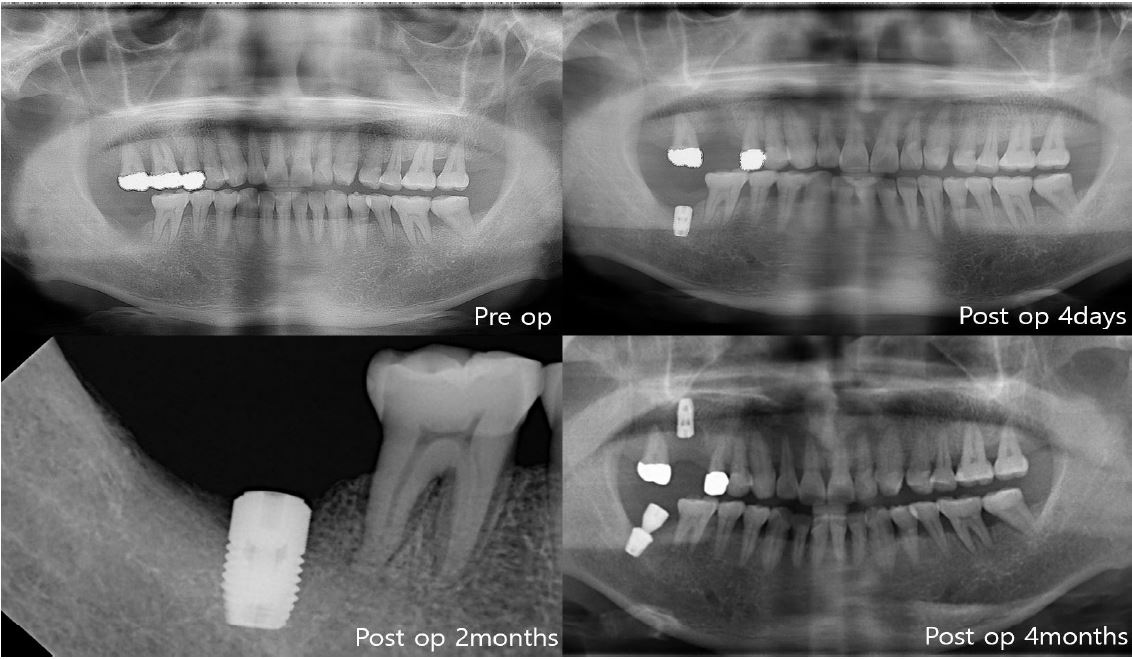

In the first case of failure, the patient had no specific medical history. The implant was removed at 6 years and 11 months (Fig. 3). In the second case, the patient had diabetes mellitus, and a smoking history. Also, GBR was performed with Xenograft and Bio-Oss. The implant was removed at 8 years and 3 months (Fig. 4). In the third case, the patient had radiotherapy history for tonsil cancer. The implant was removed at 4 years and 10 months (Fig. 5). In the fourth case, the patient had diabetes mellitus. The implant was removed, and another implant was immediately placed at four months (Fig. 6).

The first three cases of failure were classified as late failures. In one out of four cases, implant was removed at four months after implantation, and this was classified as an early failure (Fig. 6).